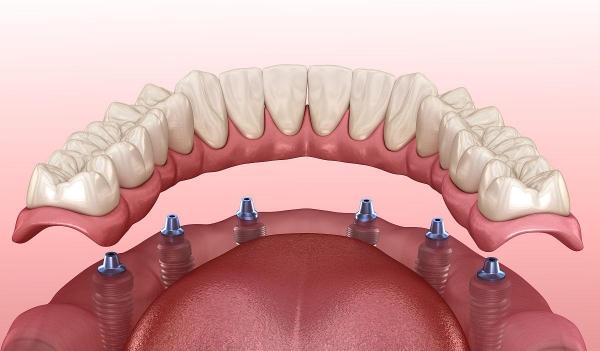

采用韩国进口种植体系统,配备数字化导板设计

核心优势:石门县少数拥有数字化种植中心的机构,正畸病例累计超500例。

设备配置:引进德国卡瓦CBCT、意大利灭菌系统,种植手术室达洁净标准。www.5#@9w.net

追求品质:康贝口腔(德国种植体 + 数字化导板)